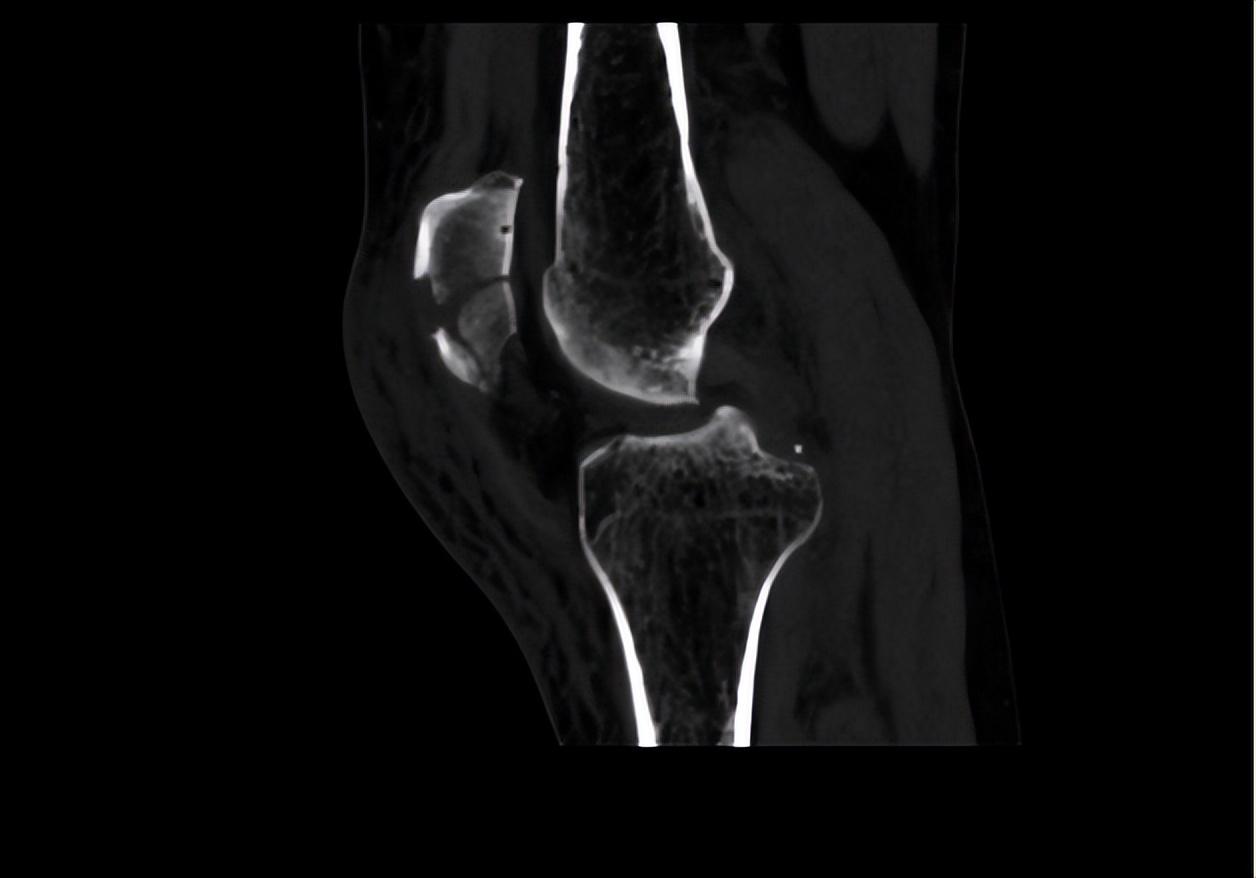

二、調(diào)節(jié)過程針對(duì)患者目前左髕骨骨折的情況,首要調(diào)節(jié)為進(jìn)行手術(shù)調(diào)節(jié),所以待患者入院后,我立刻給她開了相關(guān)檢查,以排除手術(shù)禁忌。完善血常規(guī)、肝腎功、電解質(zhì)、大小便常規(guī)、凝血功能、輸血前檢查等均未見異常。同時(shí)我也讓患者完善了心電圖、彩超、CT檢查和X影像學(xué)檢查。雙下肢彩超提示:雙下肢動(dòng)脈輕度輕度粥樣硬化。左膝關(guān)節(jié)平掃CT+二維、三維重建顯示:髕骨骨折,少量關(guān)節(jié)積液。心電圖未見異常。